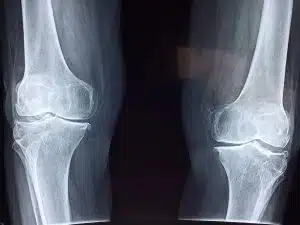

January 15, 2020While researching various specialties within medicine, you will most definitely come across the field of Orthopedics. But what is orthopedics? Orthopedics is the branch of surgery that involves the treatment of anything with the musculoskeletal system. Originally, this specialty was focused on the effects of polio in children, and developmental deformities. In the present day, orthopedics has expanded to treat all the diseases and conditions affecting the musculoskeletal system in people of every age. Some specific conditions include tumors, infections, sports injuries, spine diseases, congenital disorders, and degenerative diseases. Healthcare professionals in this field are expected to complete the proper training and education to be able to practice. Now, I’m going to break down what is orthopedics.